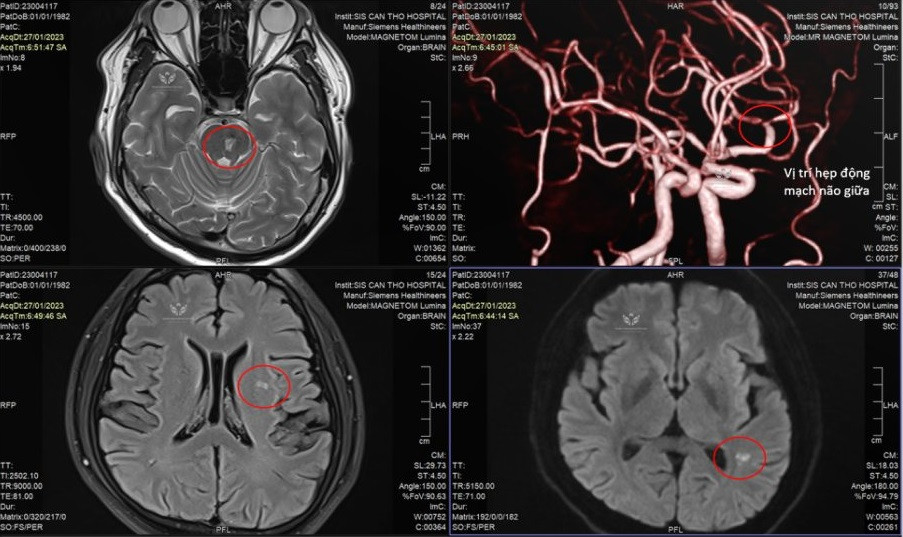

| Vùng khoanh tròn trên kết quả kiểm tra hình ảnh là vị trí nhồi máu não ở bệnh nhân |

Sáng mùng 6 Tết, người bệnh rơi vào tình trạng tê yếu nửa người bên phải nên được gia đình chuyển đến Bệnh viện S.I.S cấp cứu. TS.BS Trần Chí Cường cho biết, trên hình ảnh MRI không tiêm thuốc cho thấy bệnh nhân bị nhồi máu não do hẹp động mạch não giữa. Bên cạnh đó, kết quả xét nghiệm còn xác định người bệnh bị tiểu đường.